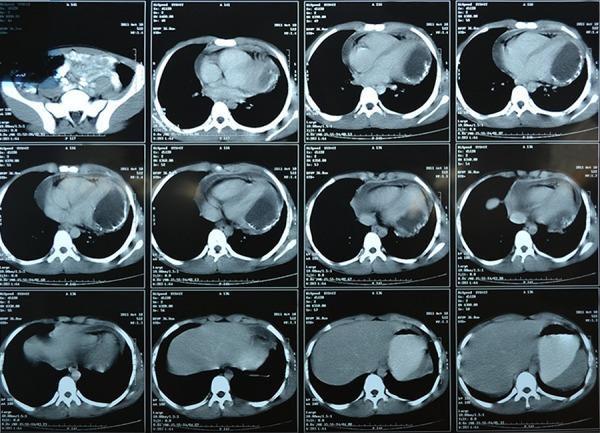

A 13-year-old boy with dyspnea and atypical pericardial type chest pain for three months was referred to us. Chest X-ray revealed linear calcification in the left side of the heart. Computed tomography demonstrated a cyst with peripheral calcification and without internal septation in the lateral left ventricle (LV) myocardium. Serologic IgG test was positive for Echinococcosis. No other cyst was seen in the other organs such as the lungs and liver. By midline sternotomy on pump, an incision was made 2-cm lateral to the left ascending artery through the LV myocardium and without entering any cardiac chamber. After injecting hypertonic (5%) saline, the cyst was punctured and its fluid contents were aspirated, the cyst was enucleated, and the cavity marsupialization was done for protection of the myocardium. LV ejection fraction before operation was 40% but after operation and repairing LV myocardium, ejection fraction increased to 50% in. Histopathologic examination confirmed a hydatid cyst.

一名13岁男孩因呼吸困难和非典型心包型胸痛3个月被转诊至我院。胸部X线显示心脏左侧有线性钙化。计算机断层扫描显示左心室(LV)外侧心肌有一个周边钙化且无内部间隔的囊肿。血清学IgG试验棘球蚴病呈阳性。在肺和肝等其他器官未发现其他囊肿。通过在体外循环下进行正中胸骨切开术,在左升主动脉外侧2厘米处经左心室心肌做一个切口,且不进入任何心腔。注入高渗(5%)盐水后,穿刺囊肿并吸出其内容物,将囊肿摘除,并对腔隙进行袋形缝合以保护心肌。术前左心室射血分数为40%,但术后修复左心室心肌后,射血分数增至50%。组织病理学检查证实为包虫囊肿。